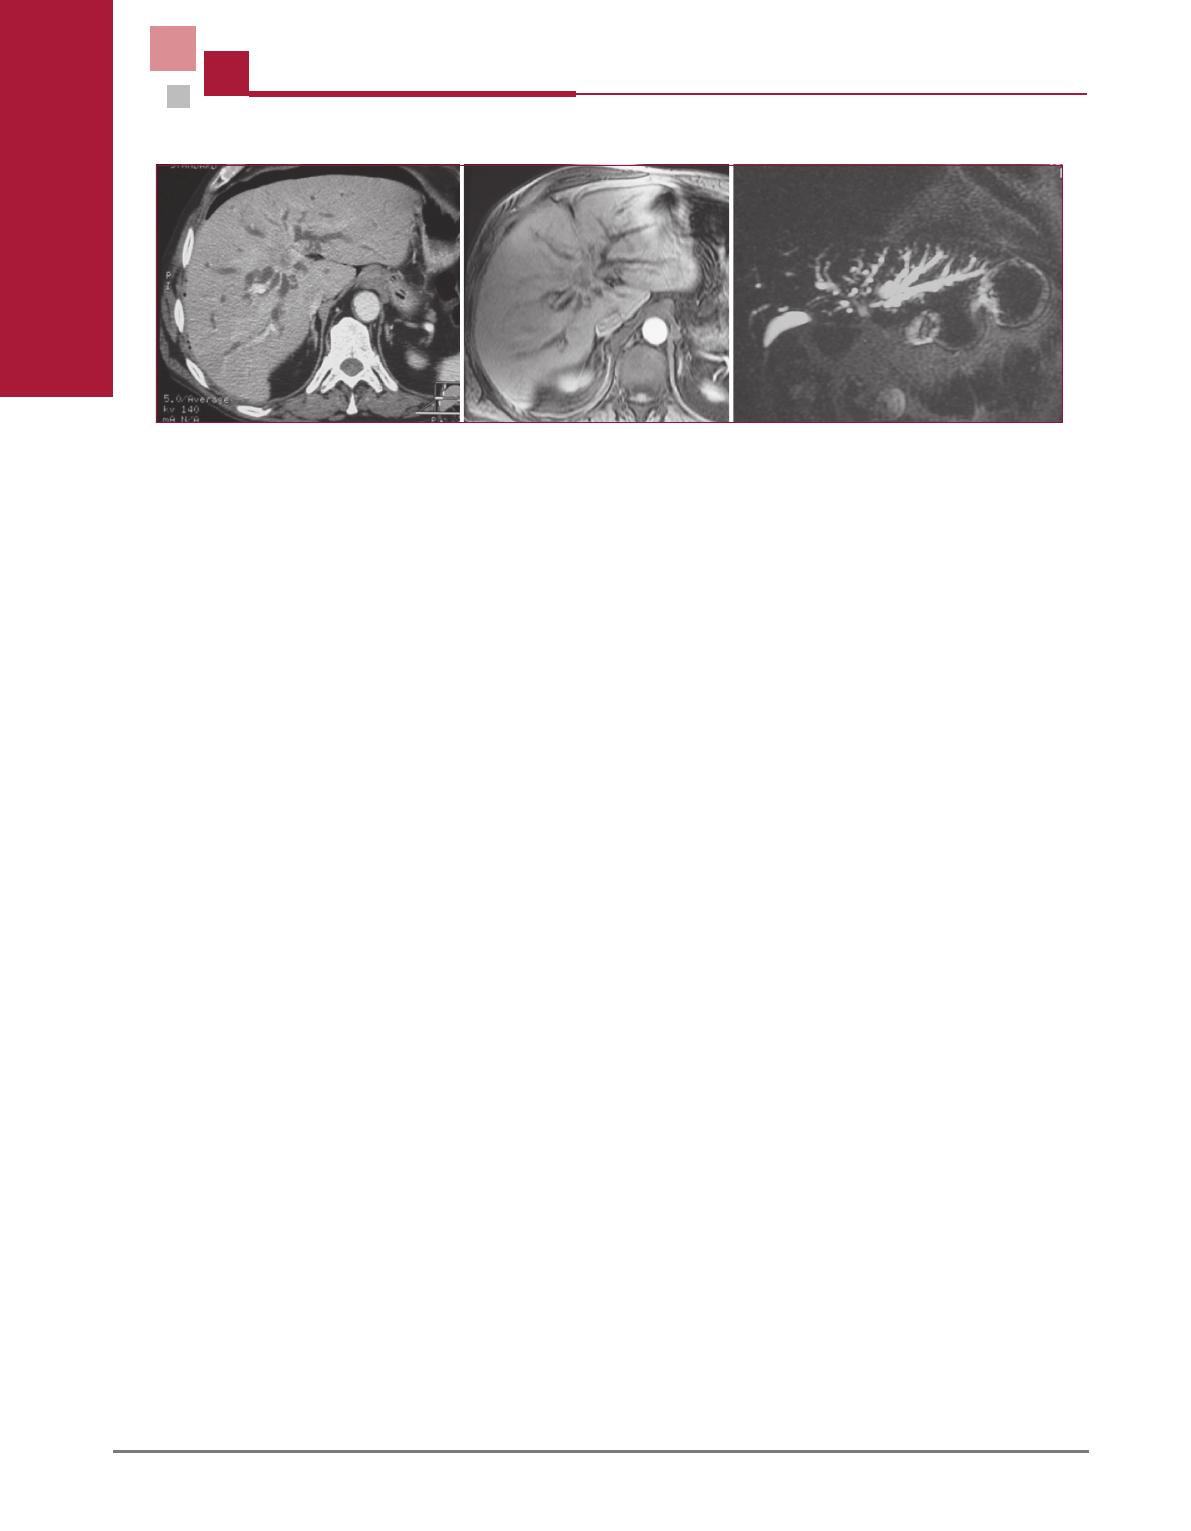

Figure 5. Photo perop

eratoire apr

es lobectomie droite, curage du

p

edicule h

epatique, r

esection en bloc de la veine porte pour

cholangiocarcinome hilaire « Neuhaus concept ». La continuit

e

biliaire est assur

ee par une anastomose biliodigestive. De la bile coule

par les canaux biliaires des segments II et III.